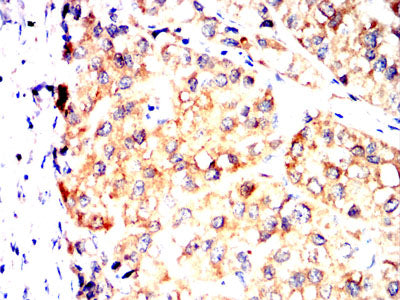

分类: 科研抗体货号: 32306别名: SCDO1应用: WB,IHC,IF,FCM反应种属: Human, Rat